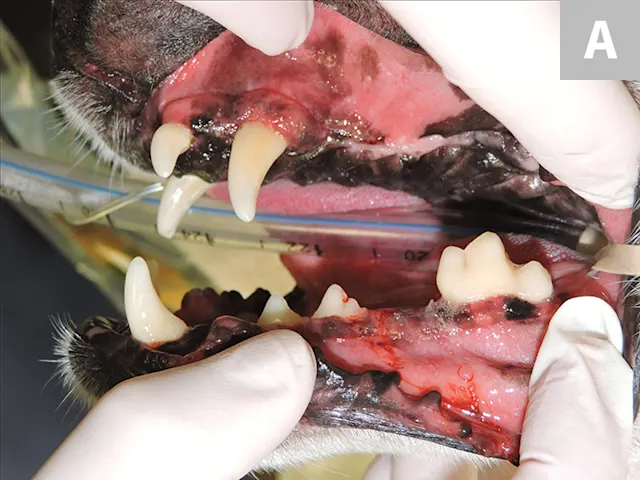

Close up of intubated dog mouth with periodontal probe pointing to oronasal fistula.

1. Root Breakage

Mucoperiosteal flaps should be developed for most extractions to allow for appropriate exposure for alveolar bone removal, which allows for better visualization and subsequent tooth root elevation.2-4 As a general rule, buccal alveolar bone should be removed before elevation is attempted to expose, at minimum, approximately half of the root.5 A small bur can be used to create a mesial and distal space to allow for placement of a dental elevator. Tooth root elevation is a slow process that fatigues the periodontal ligament; if abrupt force is applied before the periodontal ligament is fatigued or severed, the root often fractures (Figure 1). Adequately exposing soft and hard tissues at the beginning of the procedure can save time and allow for successful root removal; however, even if careful and appropriate techniques are used, roots may still break during extraction (eg, due to tooth resorption or ankylosis of the root to the alveolus). If a root breaks, additional removal of alveolar bone is often necessary to retrieve the remaining root fragment.